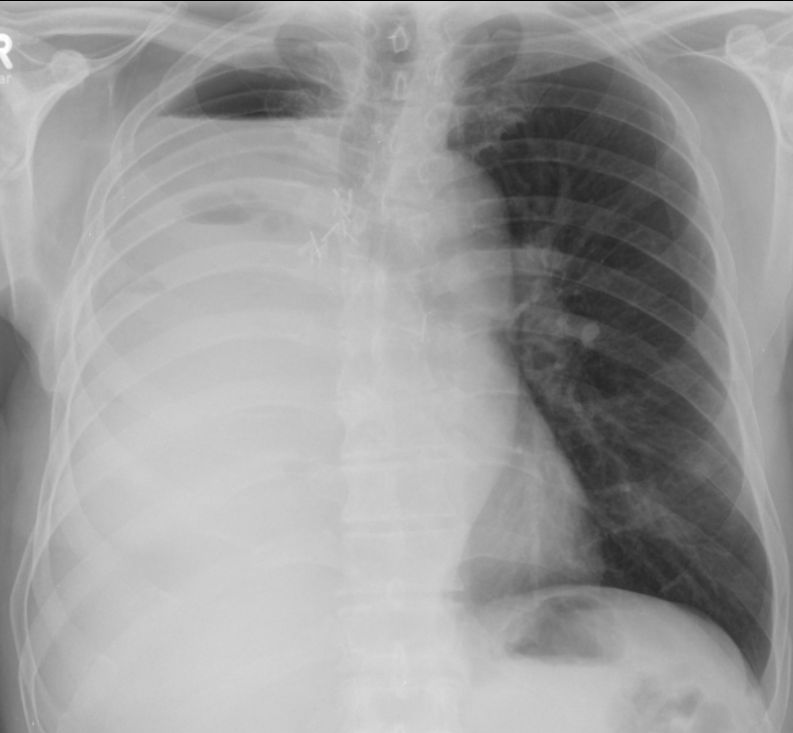

Eine Radikal - OP ist indiziert, wenn der Tumor lokal operabel ist, keine mediastinalen Lymphknoten vorliegen und Fernmetastasen fehlen. 6 Wochen nach Pneumektomie rechts.